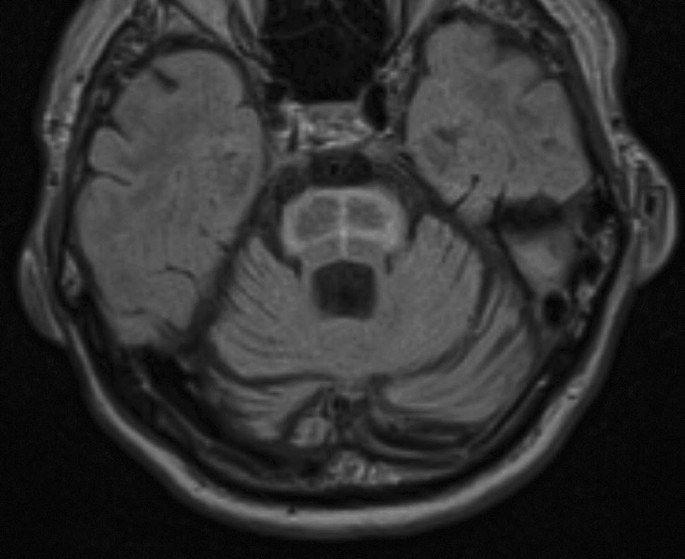

Fitness hot cross buns on cutting cartoon vector illustration. Few reports have evaluated the sensitivity of an hcb, including a cruciform. The hot cross bun sign is a radiological sign which has been said to be highly specific for multiple system atrophy. Hot cross buns are traditionally eaten on good friday on the british isles and some parts of the commonwealth such as canada and australia. The white strips represent degenerated pontine white matter pathways within the pons. Serve these warm from the oven on good friday to wow your family and friends. And friends who gift one another with hot cross buns every year. A hot cross bun is a spiced sweet bun usually made with fruit, marked with a cross on the top, and traditionally eaten on good friday in the united kingdom; Some sailors took hot cross buns on their voyages to ensure their ships wouldn't sink. The hot cross bun sign refers to the mri appearance of the pons when t2 hyperintensity forms a cross on axial images, representing selective degeneration of transverse pontocerebellar tracts and median pontine raphe nuclei. Find the perfect hot cross bun stock illustrations from getty images. If you flip to the 'bun: Oligodendrocytes comprise glial cytoplasmic inclusions (gci).

A hot cross bun is a spiced sweet bun usually made with fruit, marked with a cross on the top, and traditionally eaten on good friday in the united kingdom; Detective the hot cross buns character homemade vector illustration. Signo de la cruz (hot cross bun sign). Oligodendrocytes comprise glial cytoplasmic inclusions (gci). Hot cross buns is the perfect song for beginners: Few reports have evaluated the sensitivity of an hcb including a cruciform. And friends who gift one another with hot cross buns every year. It is the only relic that appears if the entire item pool has been exhausted. Hot cross bun sign in multiple system atrophy with predominant cerebellar ataxia: Key word signing uses a core. What are hot cross buns? Hot cross buns sign is a vommon radiographic finding in msa. Cerebellum and middle cerebellar peduncles are also atrophied.